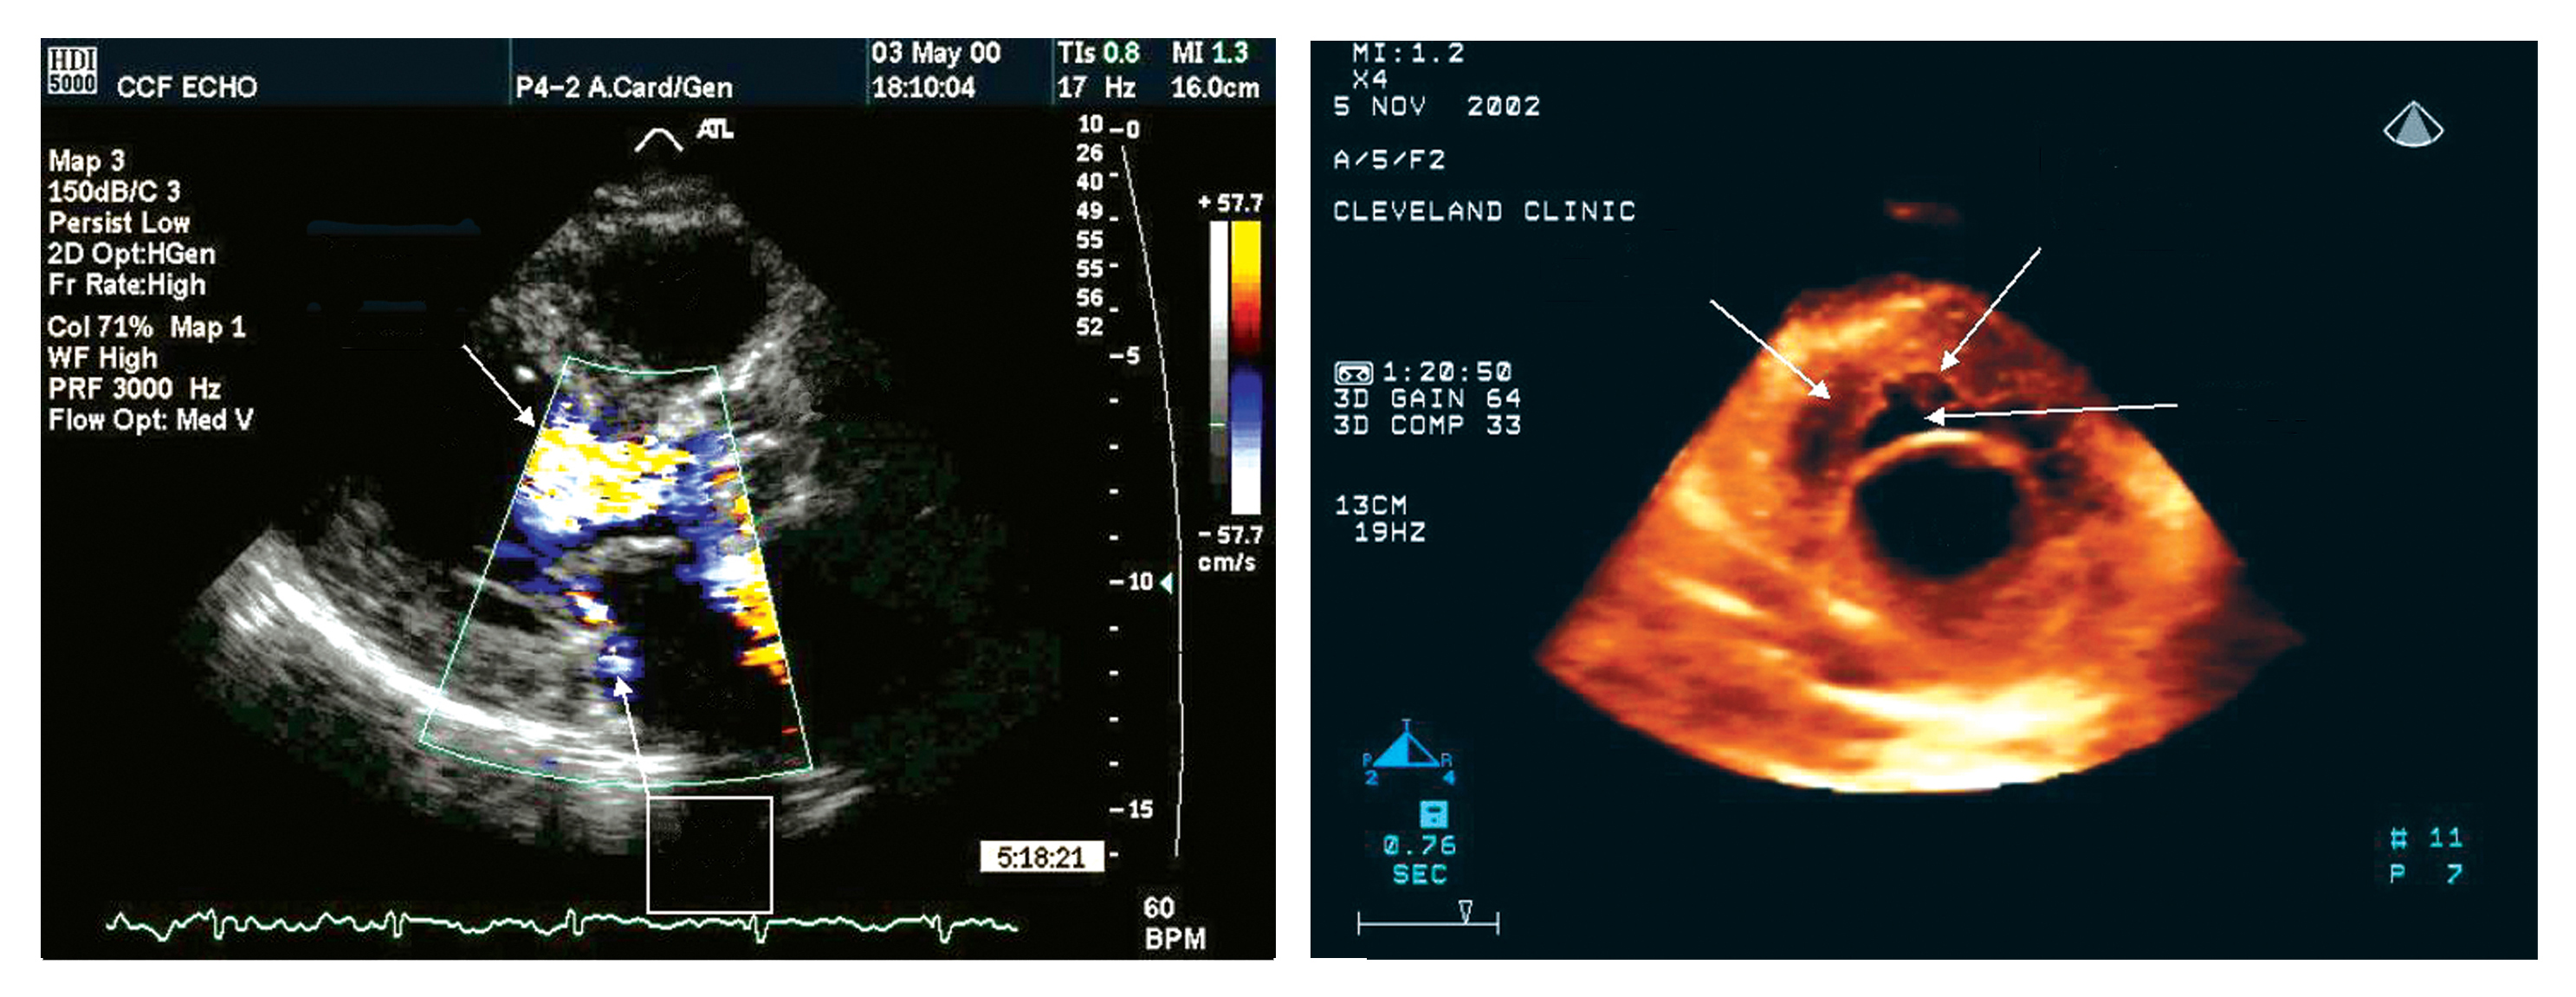

Echocardiography uses sound waves to image the heart and other organs. Developing a compact version of the latest technology improved the ease of monitoring crew member health, a critical task during long space flights. NASA researchers plan to adapt the three-dimensional (3-D) echocardiogram for space flight. The two-dimensional (2-D) echocardiogram utilized in orbit on the International Space Station (ISS) was effective, but difficult to use with precision. A heart image from a 2-D echocardiogram (left) is of a better quality than that from a 3-D device (right), but the 3-D imaging procedure is more user-friendly.